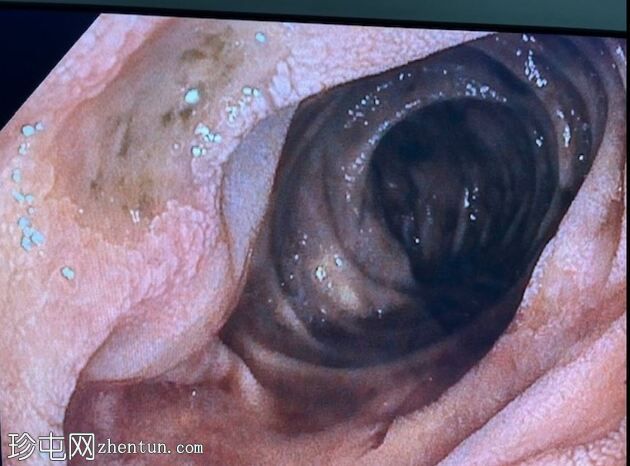

消化道内镜检查

8.jpeg

照片

十二指肠壁溃疡

9.jpeg

食管炎

止血

及止血夹

胃底可见变质血液

内镜报告:

食管:LA C级食管炎。

胃:胃底可见变质血液及大血块。吸痰、冲洗并调整患者体位以移动血块后,未在胃底或胃体部发现病变。未发现活动性出血点。

胃窦:幽门前区可见三处溃疡,每处均小于1厘米,底部均清洁。

十二指肠:

D1:D1前壁可见一处含血块的溃疡。应用两个止血夹止血,并在溃疡周围注射1:10,000肾上腺素。

D2:D2可见两处溃疡。